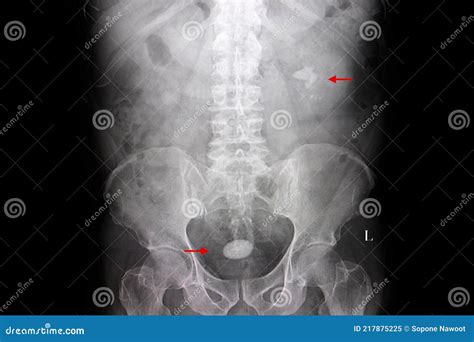

Experiencing persistent pelvic pain or difficulty while urinating can be deeply unsettling, often serving as the first warning sign that something is amiss within your urinary tract. One of the more common, yet frequently misunderstood, medical conditions affecting the lower urinary system is the presence of Stones In Urine Bladder. These solid, mineral-based deposits, medically referred to as vesical calculi, can vary significantly in size and chemical composition. While some small stones may pass naturally without intervention, others can grow large enough to cause severe blockages, infections, and intense discomfort. Understanding the underlying causes, recognizing the symptoms early, and seeking appropriate medical guidance are essential steps toward managing this condition and preventing future recurrences.

Stones In Urine Bladder are hardened collections of minerals that form inside the bladder. They typically develop when urine becomes highly concentrated, allowing minerals like calcium, oxalate, or uric acid to crystallize and clump together. Unlike kidney stones, which form in the kidneys and often travel down to the bladder, bladder stones usually originate within the bladder itself, often as a result of an inability to empty the bladder completely.

If you suspect you have Stones In Urine Bladder, a urologist will likely utilize several diagnostic tools to confirm the diagnosis. Physical examinations are often followed by imaging studies to determine the size and location of the stones. Common diagnostic methods include:

• Ultrasound: A non-invasive method using sound waves to visualize the bladder and detect solid masses.

• CT Scans: These provide high-resolution images that are exceptionally accurate at identifying even very small stones.